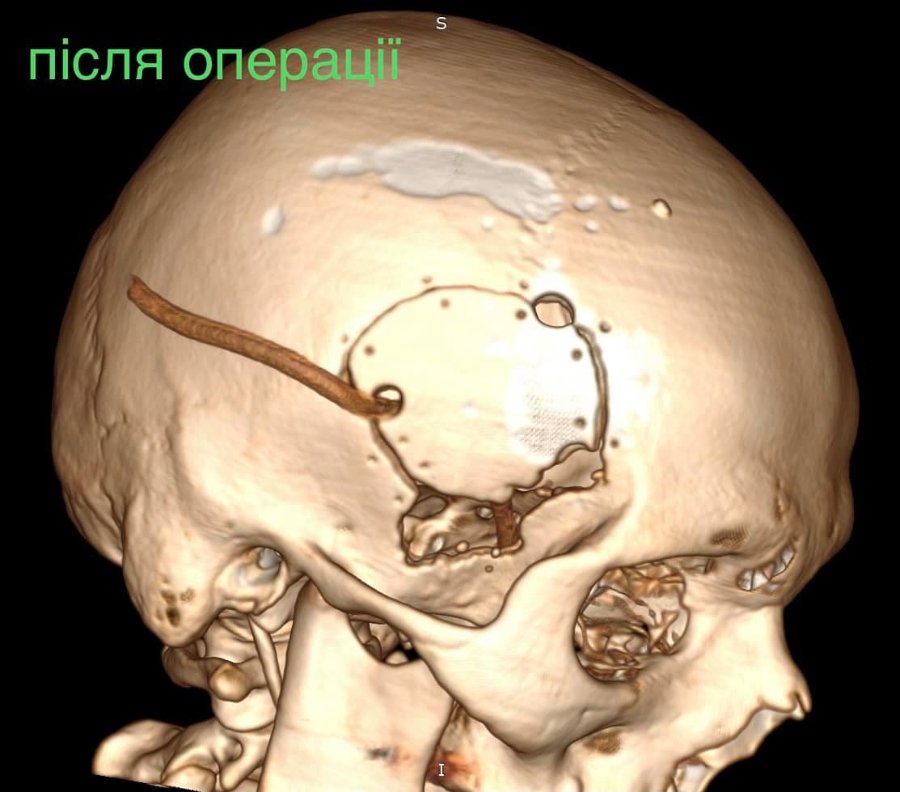

Лікарі виконали невідкладну операцію і вилучили стороннє тіло, видалили пошкоджені тканини і відновили цілісність збережених тканин.

«Добре, що куля зупинилась в 1 см від надзвичайно важливої судини і права скронева частка (яка пошкодилась в результаті травми) - функціонально незначима. Інакше, наш козак був би зовсім іншим, навзавжди», - пише лікар.